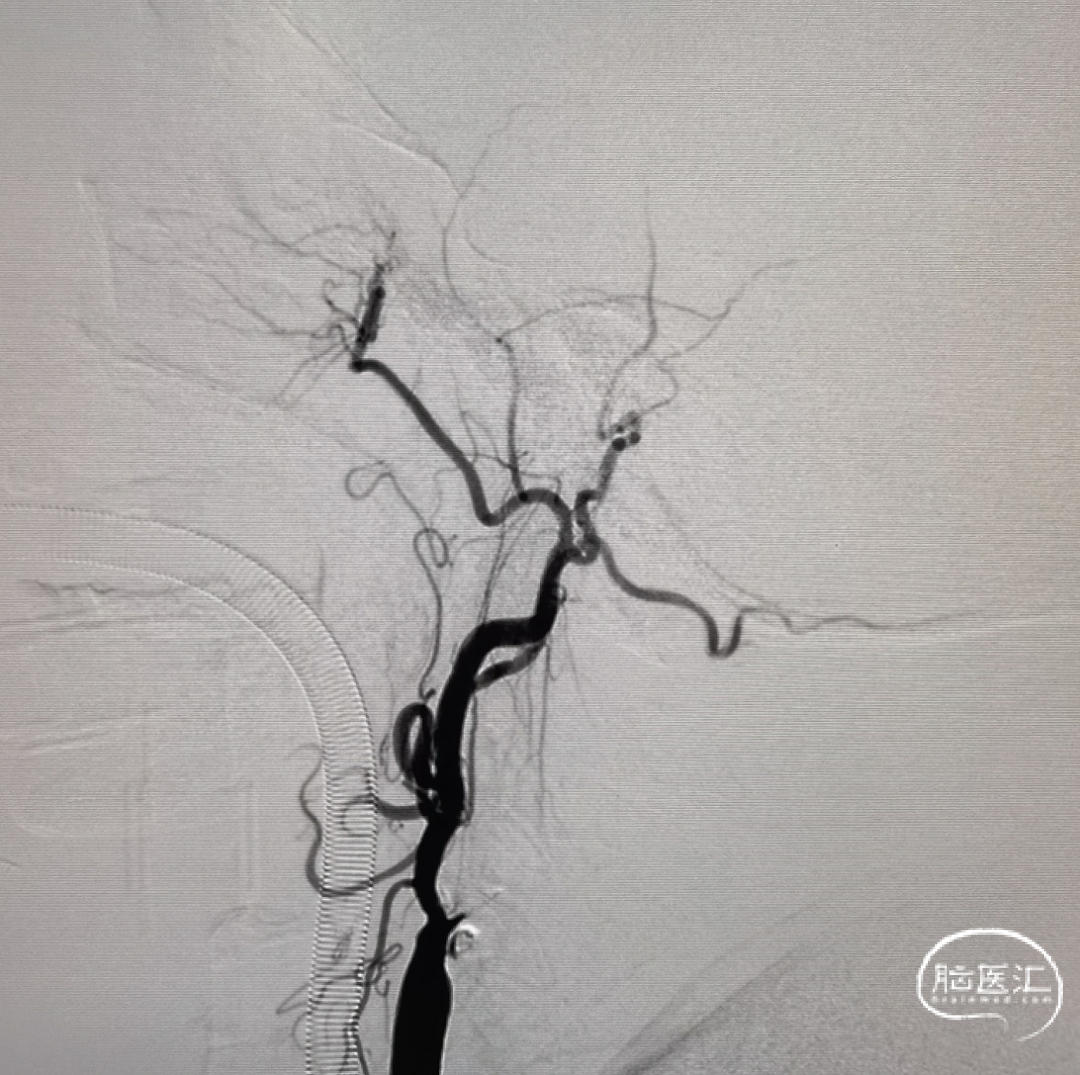

6F 115cm中间导管抽吸血栓2次后路图,见大脑中动脉、大脑前动脉闭塞。

4*30mm Syphonet®取栓支架释放后路图。

大脑中动脉取栓一把通。

术后正侧位造影:全程血流恢复满意。